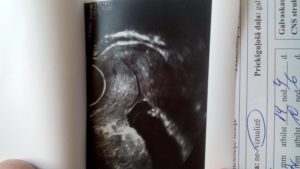

УЗИ-обследование показывает состояние внутренних органов, развитие плода и готовность женщины к родам и вынашиванию. Будущая мать на мониторе может увидеть своего ребёнка и попросить специалиста сделать фото его внутриутробного развития. Такой способ диагностики позволяет контролировать общее состояние женщины, протекание беременности и параметры шейки матки.

Наибольшую угрозу для благополучного вынашивания малыша представляет раскрытие именно внутреннего зева — той части цервикального канала, который открывает вход в матку и который не виден при осмотре на кресле. Фиксирование данного момента в ходе УЗИ является тревожным сигналом, игнорировать его ни в коем случае нельзя.

Если у беременной наблюдаются такие симптомы, как тяжесть внизу живота; чувство распирания во влагалище, обильные выделения, врач проводит гинекологическое исследование с помощью зеркала и назначает трансвагинальное УЗИ, которое точно обследует шейку матки и определит, что внутренний зев закрыт.

Для определения патологии необходимо ультразвуковое исследование с помощью вагинального датчика (такой метод более эффективный).

В процессе обследования специалист оценивает состояние шейки матки, длину и наличие раскрытия внутреннего зёва. При ИЦН орган имеет V-образный вид.